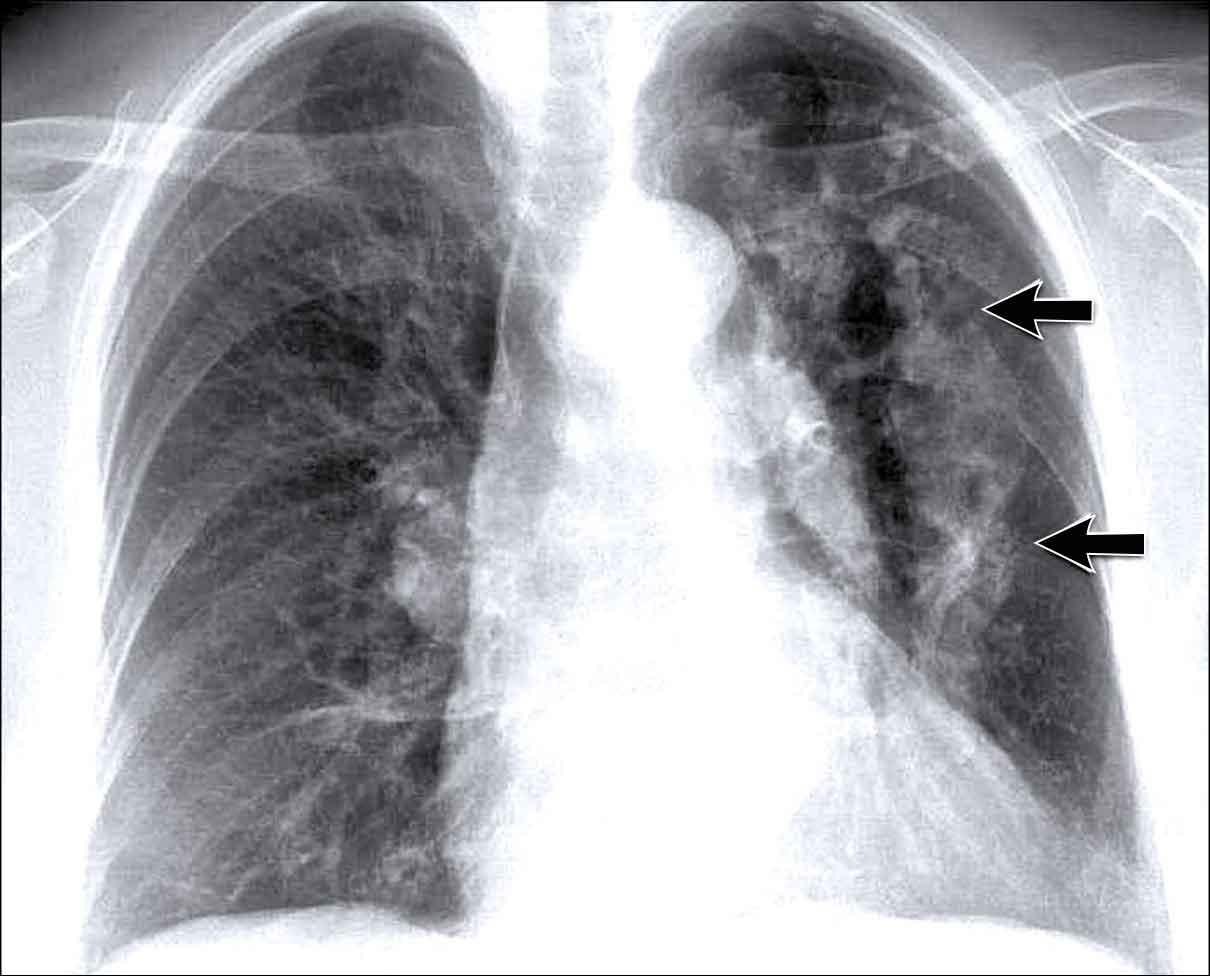

To rốn phổi – ca 1

Trong trường hợp này, bóng rốn phổi to ra ở cả hai bên. Nguyên nhân có thể do mạch máu giãn to hoặc hạch bạch huyết to. Một dấu hiệu rất có giá trị trong trường hợp này là khối nằm bên phải khí quản.

Đây được gọi là dấu hiệu 1-2-3 trong bệnh sarcoidosis, tức là to rốn phổi trái, rốn phổi phải và hạch cạnh khí quản.

Dưới đây là thêm một số ví dụ về bệnh sarcoidosis.

Nhấp vào hình để phóng to.

- Hạch bạch huyết to và hình ảnh kính mờ (ground-glass) ở phổi

- Hạch bạch huyết to, dấu hiệu 1-2-3

- Hạch bạch huyết to khối lớn

- Dấu hiệu 1-2-3

- Hình ảnh nốt ở phổi, không có hạch bạch huyết to

- Hạch bạch huyết rốn phổi và cạnh khí quản to